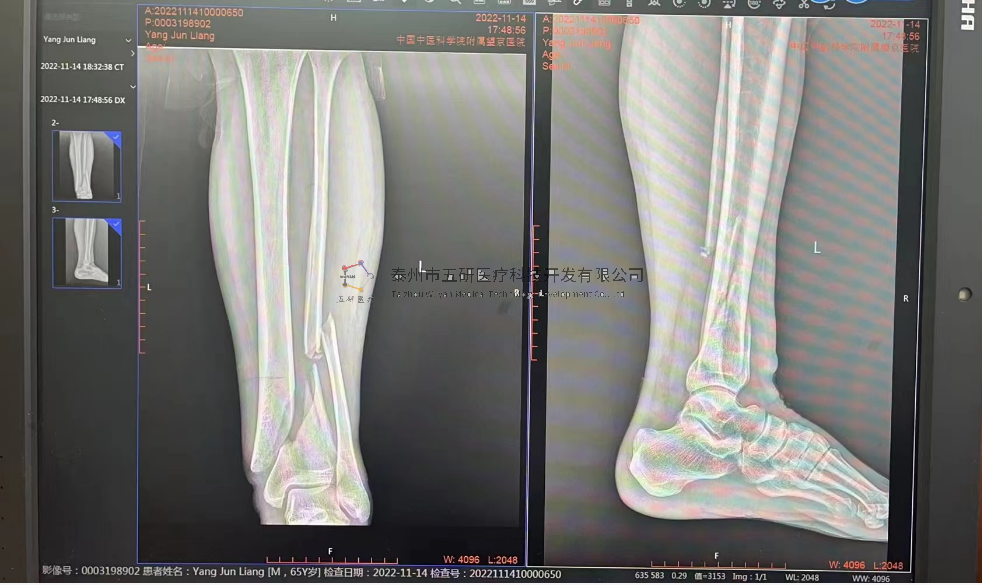

// 下肢骨折

【所屬科室】中國(guó)中醫(yī)科學(xué)院望京醫(yī)院創(chuàng)一科

【基本資料】患者,男,65歲

【患者情況】脛骨遠(yuǎn)端骨折伴腓骨骨折

【影像圖片—術(shù)前】